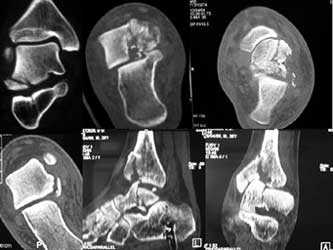

Рентгенограмма, КТ при переломе шейки и головки таранной кости

Переломы таранной кости, даже со смещением, достаточно сложны для диагностики и требуют значительного опыта у врача. Как правило, многие переломы таранной кости не всегда удается рассмотреть на первичных рентгенограммах. Компьютерная томография дает гораздо больше информации. КТ незаменима при планировании операции. По нашему мнению, КТ с 3D-моделированием должна выполняться всем пациентам без исключеня перед хирургическим вмешательством.

Также с помощью КТ и МРТ возможно выявить не видное на обычных рентгенограммах повреждение хряща таранной кости.